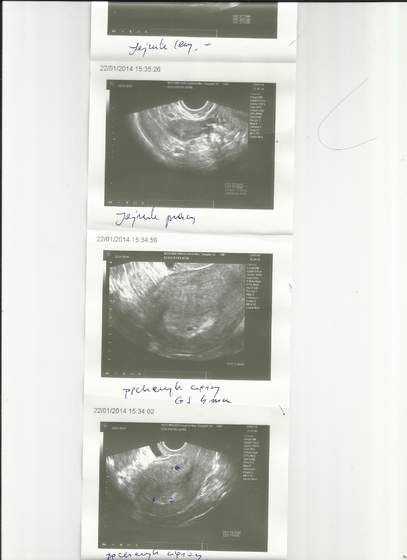

![usgstyczen [uuusssgg].jpg usgstyczen [uuusssgg].jpg](https://fx1.bbstatic.pl/attachments/339/339015-3e5a02cc75739e6d35454dc5eb42bf56.jpg?hash=PloCzHVznm)